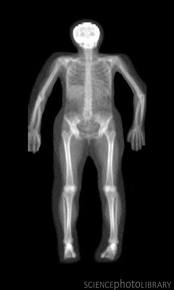

The most non-invasive diagnostic test to determine bone health is the bone mineral density. “There are two types. Central is a measure of the density of the mineral of the bone in the spine and hip and peripheral measures the density in the wrist,” explains Dr. Hanna Mawlad, nephrologist at University of Kentucky Chandler Hospital. Some peripheral measures are x-rays while others are ultrasounds. It is indicated for postmenopausal women as well as men after the age of sixty-five. If you have a history of fracture, it is a good idea to test earlier. “Based on the World Health Organization classification, we can use this test to see if the patient has osteopenia, osteoporosis or normal bone mineral density,” says Mawlad.

There is one chief disadvantage of the bone mineral density test. “It gives you an idea about the quantity but not the quality or whether the bone is healthy. For the quality, you have to do a bone biopsy and study the bone under a microscope,” says Dr. Hartmut Malluche, professor and chief of the division of nephrology, bone and mineral metabolism at University of Kentucky Chandler Hospital. The biopsy is the gold standard which allows you to see the pathology.